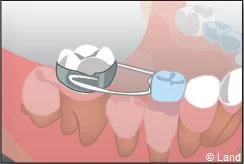

Lorsque des dents de lait ont été extraites trop tôt parce qu’elles étaient cariées, les dents de part et d’autre peuvent migrer et combler l’espace, bloquant ainsi l’éruption des dents définitives. Il est alors nécessaire de maintenir cet espace avec un appareillage spécifique appelé « mainteneur d’espace » jusqu’à l’évolution des dents définitives.

De plus, il est opportun de corriger très tôt certaines malpositions. Les appareils généralement utilisés sont amovibles avec une armature en résine, mais peuvent aussi être fixes à l’aide de bagues sur les premières molaires définitives.. Suivant leurs conceptions et la manière dont ils sont portés, ils auront une action sur la position des dents mais aussi sur la croissance.